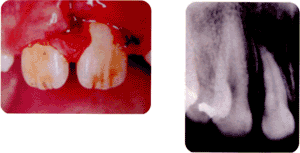

(埋入の写真)

歯には問題なく埋まってしまった状態。根が出来ていない時(根未完成歯)は、根の成長に経過を観ていく。

(骨折の写真)

下の顎が前歯2番目と3番目の間で折れている。

(骨折のレントゲン)

左下の親知らずの所で折れている。親知らずは、その歯のある所が骨が薄くなっているので外傷等で骨折しやすい。